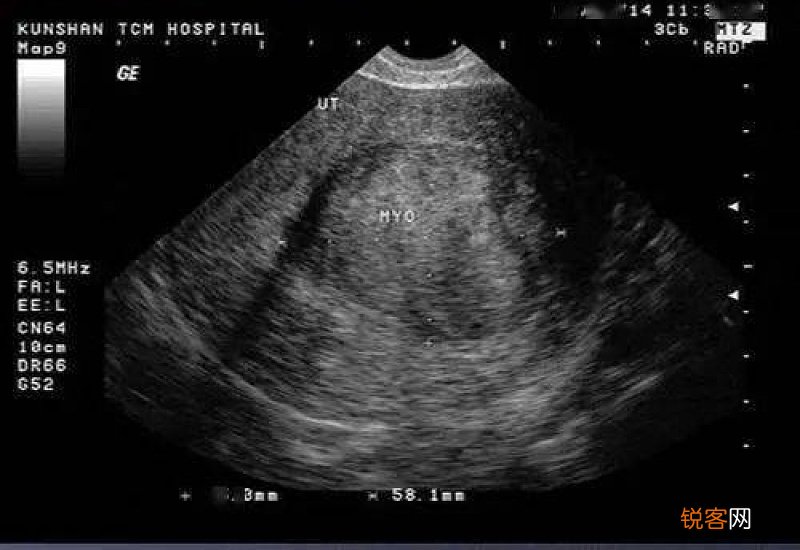

妇科b超可以检查子宫及附件的大小、结构及占位,可以判断是否有子宫及附件肿瘤、卵巢囊肿等实质性的病变,还能够观察盆腔是否有积液以及积液量的多少 。对 女性的子宫肌瘤、子宫内膜息肉、增生以及盆腔炎症都可初步判断,而且在备孕的过程当中 , 通过B超还可以了解女性的卵泡发育、排出情况 。